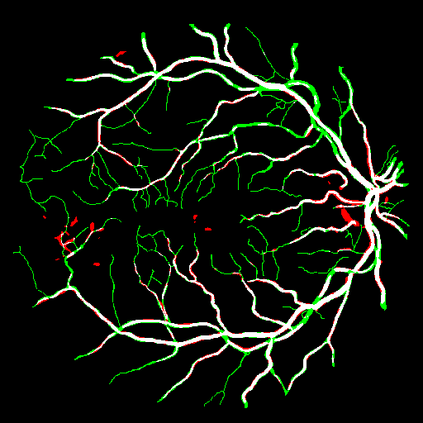

Vessel segmentation is an essential task in many clinical applications. Although supervised methods have achieved state-of-art performance, acquiring expert annotation is laborious and mostly limited for two-dimensional datasets with a small sample size. On the contrary, unsupervised methods rely on handcrafted features to detect tube-like structures such as vessels. However, those methods require complex pipelines involving several hyper-parameters and design choices rendering the procedure sensitive, dataset-specific, and not generalizable. We propose a self-supervised method with a limited number of hyper-parameters that is generalizable across modalities. Our method uses tube-like structure properties, such as connectivity, profile consistency, and bifurcation, to introduce inductive bias into a learning algorithm. To model those properties, we generate a vector field that we refer to as a flow. Our experiments on various public datasets in 2D and 3D show that our method performs better than unsupervised methods while learning useful transferable features from unlabeled data. Unlike generic self-supervised methods, the learned features learn vessel-relevant features that are transferable for supervised approaches, which is essential when the number of annotated data is limited.